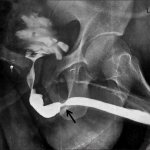

- انجام گراف رنگی از مجرای ادراری که می تواند شدت ،محل و طول تنگی در مجرا را نشان دهد .